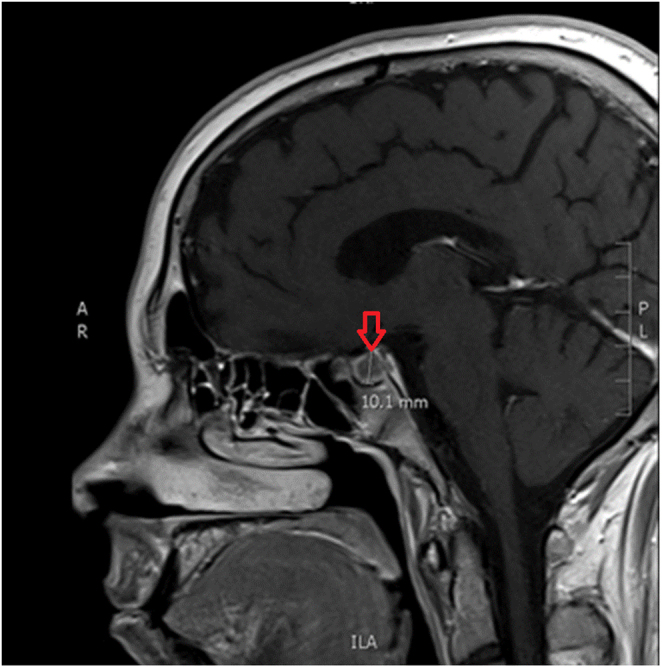

Summary: Cushing's disease (CD) is characterized by distinct syndromic features, often accompanied by obesity and depression. However, considering its gradual onset of symptoms, it is usually associated with diagnostic delays. In rare instances, CD may lead to severe infections due to the observed immunosuppression in affected individuals. We present a rare case of an undiagnosed CD in a 20-year-old male with a medical history of depression and obesity, complicated by severe COVID-19 infection. He presented to the Emergency Room with respiratory distress, hypertensive crisis, and fever, ultimately receiving the diagnosis of SARS-CoV-2 pneumonia. The patient required mechanical ventilation and intensive care unit (ICU) admission due to severe acute respiratory distress syndrome (ARDS). During ICU care, he received remdesivir and dexamethasone, subsequently developing severe hyperglycemia and worsened hypertension, requiring insulin and multiple antihypertensive agents to manage metabolic disruption. Upon physical examination, classic signs of hypercortisolism were noted. Subsequent laboratory tests and pituitary magnetic resonance imaging confirmed the diagnosis of CD. The patient underwent surgical resection with significant improvements in body composition and metabolic parameters postoperatively. After surgery, remission of hypercortisolism was evident, accompanied by notable improvements in mood and overall health. This case underscores the importance of recognizing hypercortisolism in the context of metabolic, physical, and mood changes. Timely diagnosis of CD is crucial to mitigate complications such as severe opportunistic infections and their outcomes.